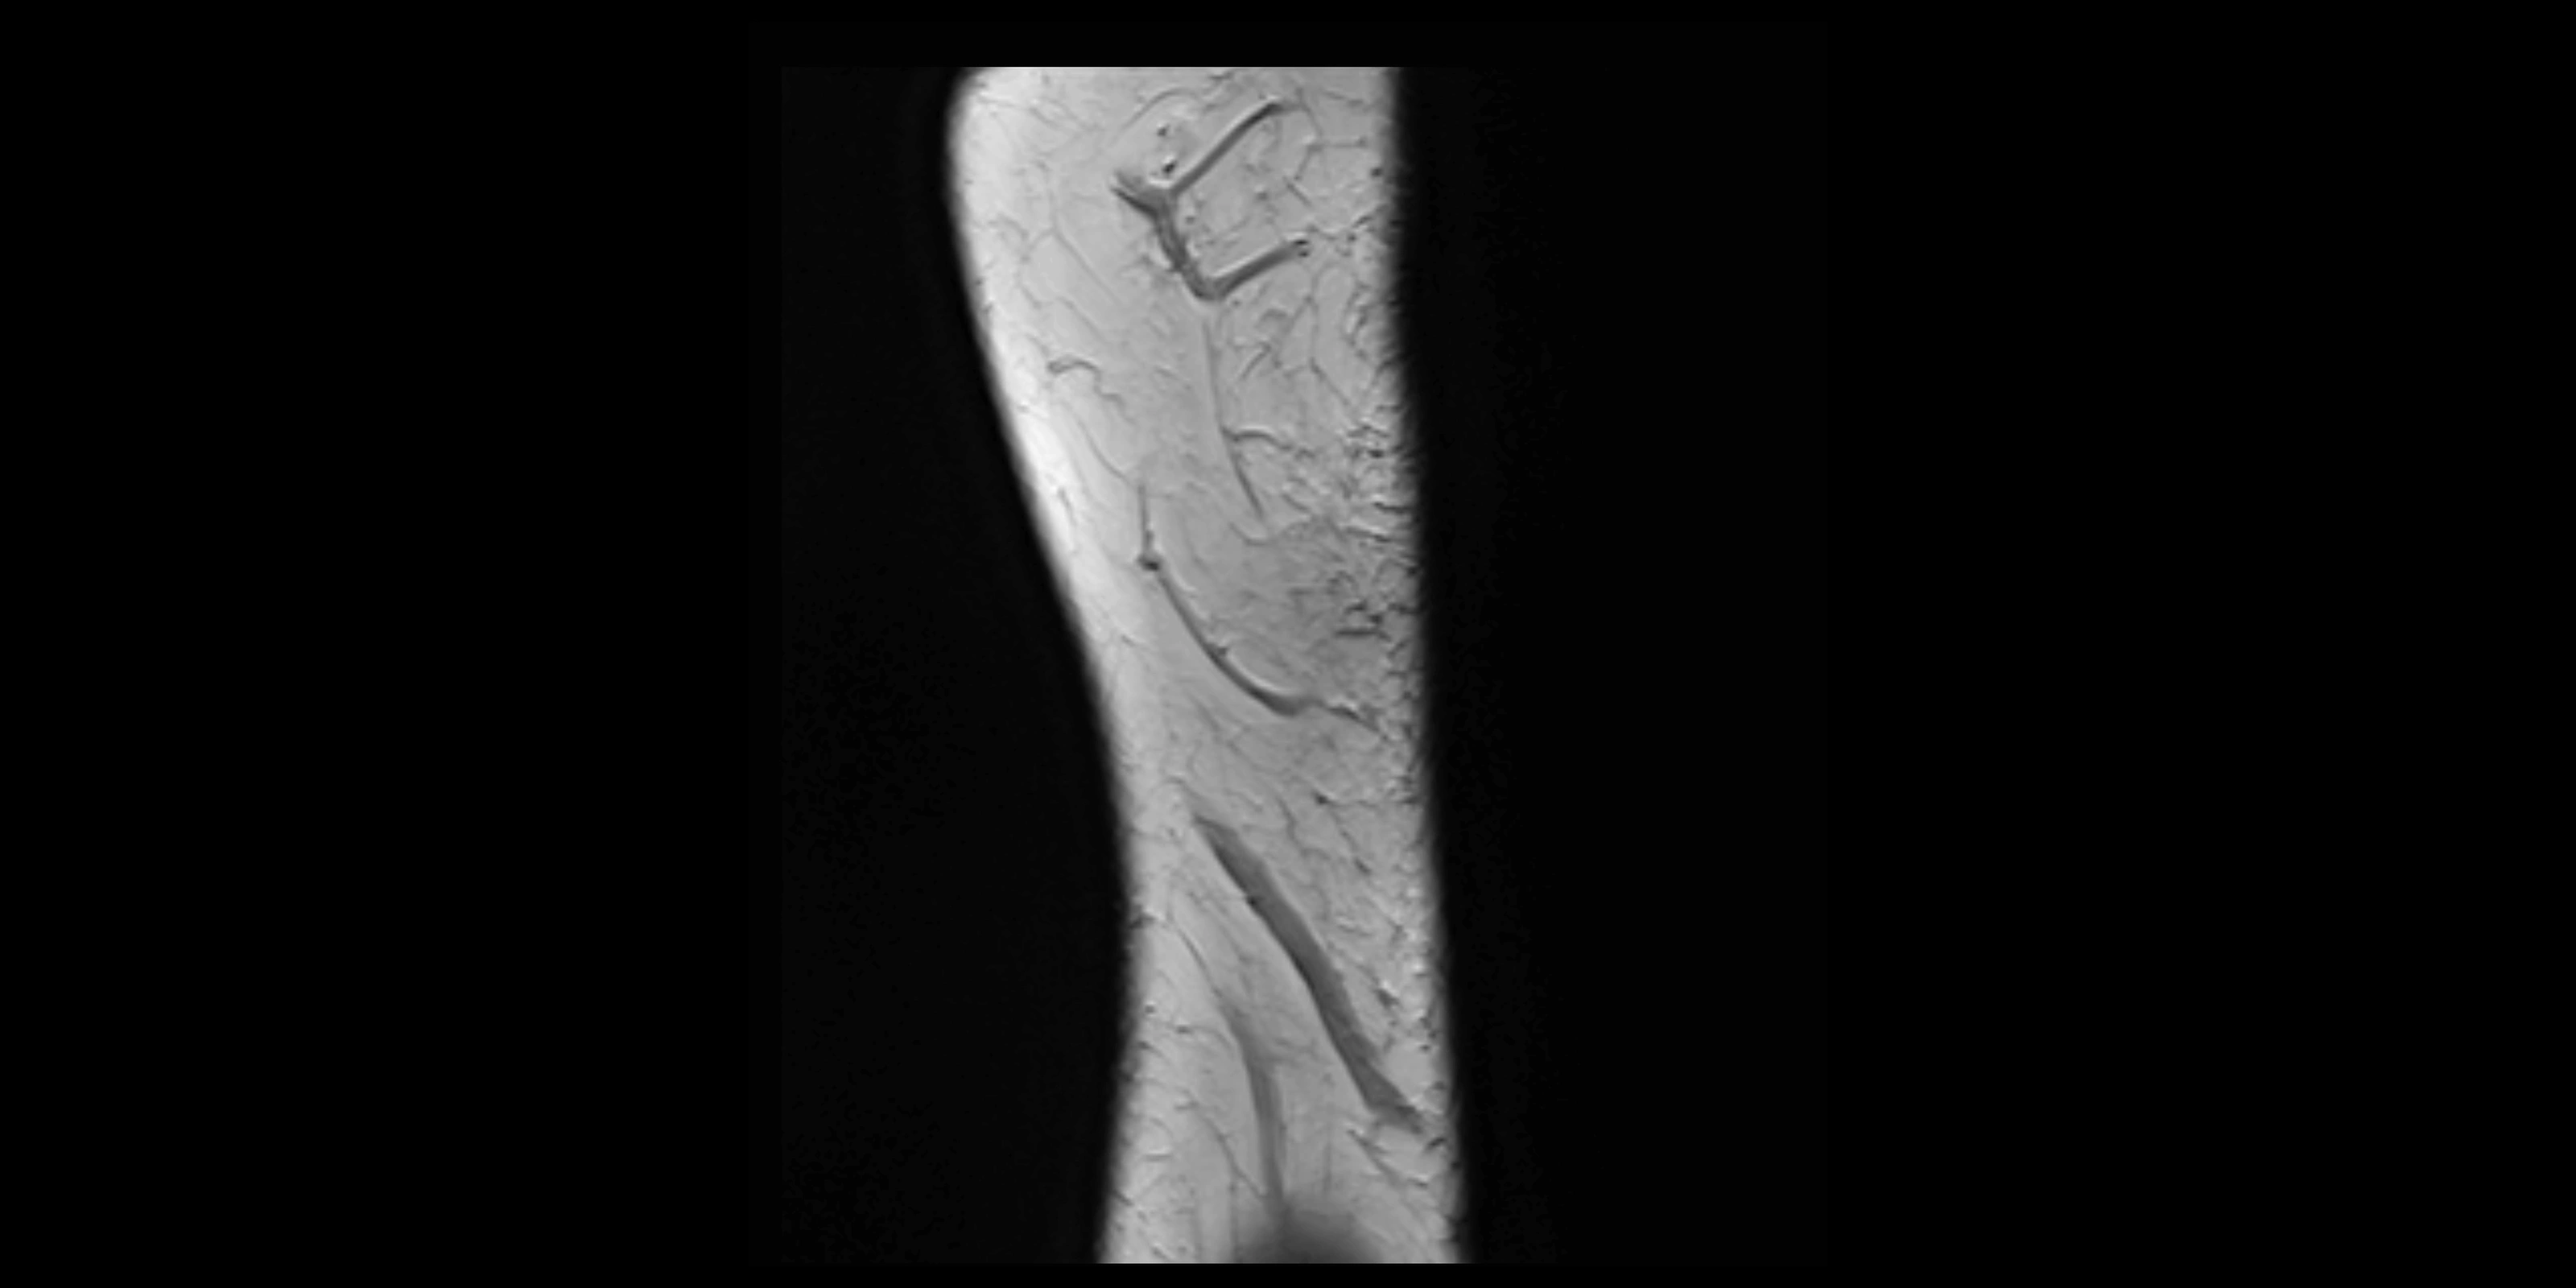

CT Appearance

Non-Contrast CT:

• Ligament not directly visualized due to soft-tissue density but may be inferred by the radial head’s containment in the notch.

• Bony margins of the radial notch and radial head appear smooth and congruent in normal anatomy.

• Avulsion injuries: subtle cortical irregularity or small bone fragments at ulnar attachment.

• Chronic cases: periarticular calcifications or ossification along ligament attachment.

CT Arthrogram Appearance

• Contrast fills the proximal radioulnar joint and outlines the radial head.

• Normal annular ligament: appears as a smooth, thin ring confining contrast to the joint space.

• Partial tear: contrast seeps beneath ligament or into adjacent soft tissues.

• Complete tear or dislocation: contrast extravasates around the radial neck or ulnar radial notch.

• Highly effective for evaluating joint congruency, ligament integrity, and subluxation when MRI is unavailable or contraindicated.

MRI images

image